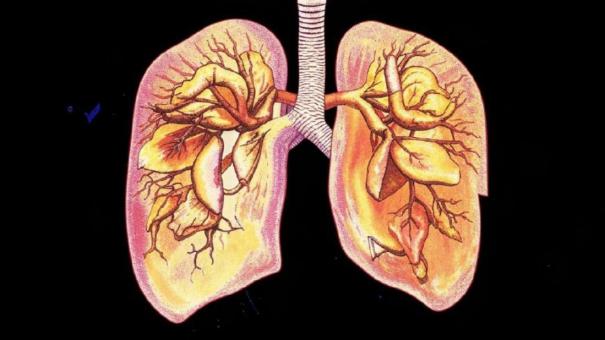

В Новосибирской области каждый четвёртый житель курит, что составляет 26% населения. Эта вредная привычка может привести к развитию опасных заболеваний. Среди которых особое внимание уделяется облитерирующему бронхиолиту, который чаще всего поражает молодых людей. Главный пульмонолог региона Любовь Куделя подчеркнула, что курение может вызвать два серьёзных заболевания: хроническую обструктивную болезнь лёгких (ХОБЛ) и облитерирующий бронхиолит, сообщает ТАСС.

ХОБЛ, характерный для курильщиков старше 45 лет, и облитерирующий бронхиолит, который может развиться уже у людей от 20 до 35 лет, представляют серьёзную угрозу здоровью. Пульмонолог Любовь Куделя предупреждает, что каждый второй курящий человек рано или поздно столкнется с ХОБЛ.

В Новосибирской области уже зарегистрировано около 16 тысяч человек, страдающих ХОБЛ. Однако специалисты уверены, что реальное количество больных может быть гораздо выше, из-за того что некоторые обращаются за помощью уже на поздних стадиях заболевания.